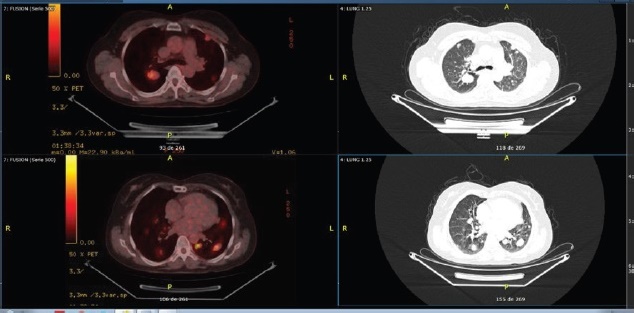

Como la primera técnica validada de “imágenes metabólicas”, tanto en la ciencia básica como en entornos clínicos, la FDG es el trazador PET más utilizado para la obtención de imágenes de tumores malignos. Una tasa acelerada del metabolismo de la glucosa, mediada por la regulación positiva de enzimas y transportadores glucolíticos (GLUT), es característica de la transformación maligna, un fenómeno reconocido desde hace más de ocho décadas. Sin embargo, en los tumores de tiroides, el aumento de la captación de FDG se limita a neoplasias malignas más agresivas y de alto grado, y los tumores bien diferenciados muestran una captación insignificante del trazador. Se cree que la relación inversa entre la captación de 131I y 18F-FDG en el carcinoma de tiroides, conocida como fenómeno “flip-flop”, se debe a una pérdida de la capacidad de concentración de 131I durante la desdiferenciación combinada con una mayor demanda de glucosa por parte de las células tumorales 11 (Fig. 1).

Fig. 1 Ilustra un caso extraído de nuestra práctica clínica habitual, correspondiente a una paciente de 57 años diagnosticada con carcinoma folicular bien diferenciado. En octubre de 2010, se sometió a una tiroidectomía total. El examen histopatológico reveló la presencia de un adenoma folicular con un patrón trabecular y células oncocíticas, sin invasión capsular ni evidencia de invasión vascular. En 2015, una radiografía de tórax reveló un nódulo pulmonar de 3 cm. Para octubre de 2018, los niveles de tiroglobulina se encontraban elevados, y un rastreo con yodo radiactivo (131I) no mostró captación del radioisótopo. Posteriormente, se realizó un estudio con 18F-FDG PET/CT, que demostró la presencia de múltiples nódulos pulmonares hipermetabólicos, con un Valor de Captación Estándar (SUVmax) 8.1, con diámetros de hasta 33 mm y se distribuían en las regiones centrales y periféricas de ambos campos pulmonares. Dichos hallazgos son indicativos de un proceso de desdiferenciación y progresión de la enfermedad oncológica.